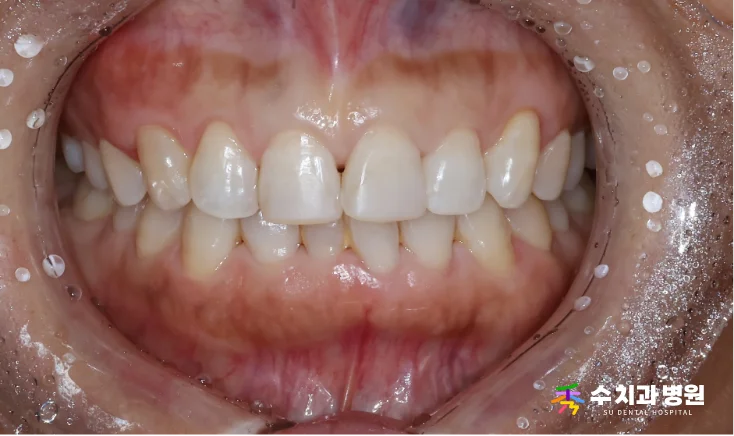

[📸 치료 전 사진] (촬영일: 2025년 8월)

10년 전부터 앞니 변색이 진행된 상태였고,

미소를 지을 때마다 신경이 쓰인다고 하셨습니다.

검진 결과 위 앞니 일부가 어둡게 변해 있었습니다.

특히 왼쪽 위 첫 번째 앞니는 약간 틀어져 있었습니다.